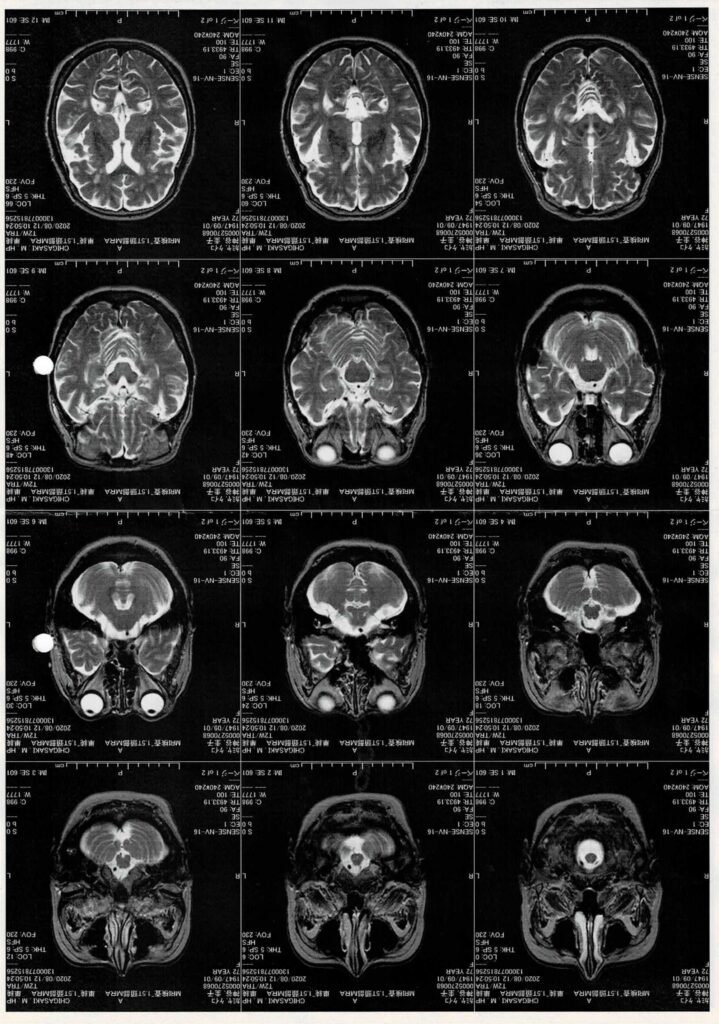

喉の奥の扁桃腺が異常に大きいと言われ、風邪ばかり引くのはそのためだと、複数の医師を訪ね回りました。そしたら、名前は忘れましたが、ある医師から自分は診断治療できないが、この子は、舌の先から歯茎にかけて組織が伸びているために、舌の動きが制限されています。先天性の病気で、このままではこの子は自立できませんよ、と言われました。

私達は慌てた、青くなった。可哀想だ。何とか、治療出来る医者はいないか?調べるうち、昔は、お産婆さんが、舌を確認して、「つれ舌」を切って、治したと言う話を聞いて、調べるうち、大和市に舌の専門医がいるとの情報を得た。

大和市、舌、兎に角、藁をもすがる気持ちで、電話をしました。当たった。この子にはまだ未来があるのだ。と思った。胸が痛かった。同じような病の方々が沢山ベンチに座っていた。

神谷サンと呼ばれる。初老の先生が、早くて良かったね。といい、舌は切っとくから大丈夫、扁桃腺も取っておこう。大きすぎる。これは、多動性の原因なんですよ。少しは改善するでしょう。歌、歌えるよになりますから、話もできるようになるでしょう。はじめの難関は超えた。

⑤H病院の先生の診断

注意欠陥多動性障害児の反社会性の強い状態との診断で、反社会性の発作を抑えるために、精神安定の措置を病院で行いました。結局3か月の入院となつた。

⑥毎週妻と病院に会いに行った。病院診断は、今後の方向のアドバイスをもらう為てした。数学性と音などの分野は、優れているから、反社会性を抑えれば、道はあると言われた。

⑦退院後、東大医学部で実績の心療内科が茅ヶ崎にできた。

先生は、司馬先生と同意見の方だった。反社会性を薬で抑えて、自由業で生きて行く。反社会性の傾向は、40才ごろで少なくなるから、辛抱して、育てて下さいだった。